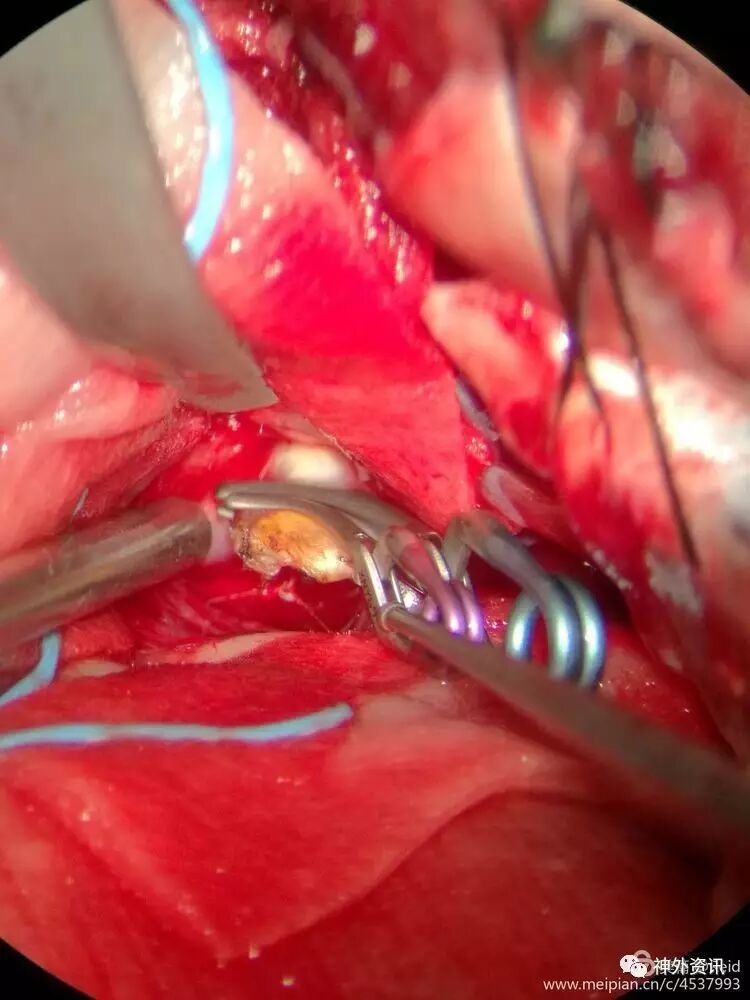

可见基底动脉尖动脉瘤颈,瘤壁呈淡蓝色,菲薄,基底动脉临时阻断状态下动脉瘤体张力不高。

小心剥离动脉瘤颈前、后方,仔细辨认穿支血管,小心保护,之后以一枚mini动脉瘤夹顺利夹闭动脉瘤颈,瘤体缩小,瘤颈右侧根本没有空间暴露及窥视,祈祷没有穿支血管误夹。